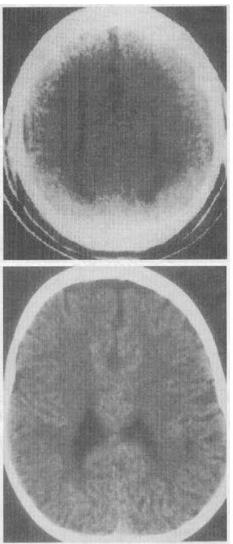

- 单项选择题 患儿男性,19个月。至今不能站立、不会说话。根据CT扫描所见〔见图),应诊断下列哪一种疾病()。

- E